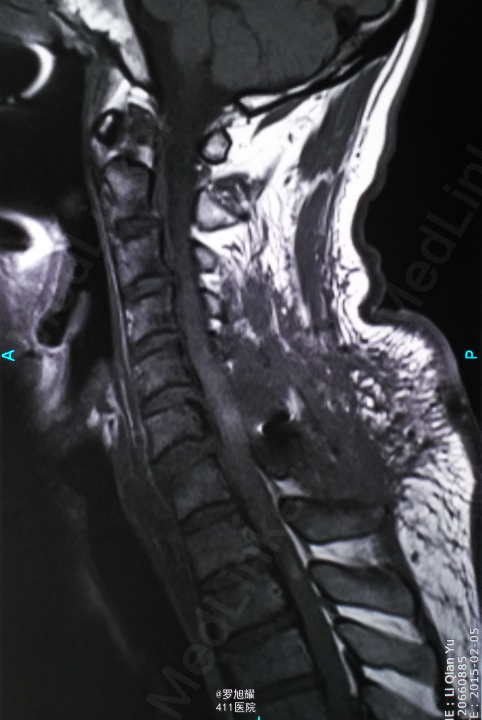

查体:双上肢前臂及以远感觉丧失,躯体自第二肋间平面以下感觉丧失。耸肩可,双侧三角肌、肱二三头肌肌力2级,腕关节屈伸、旋转及各指肌力0级。腱反射阴性,但球海绵体反射已经阳性。影像学检查示颈椎骨折脱位伴颈髓损伤。

诊断:颈6/7骨折脱位伴高位截瘫。处理:立即甲强龙冲击、脱水、保胃、营养神经治疗。首选治疗方案是颅骨牵引复位后前路融合固定,较后路稳定,出血也少,和家属谈话后开始颅骨牵引复位,4kg起步,每半小时增加1kg直至14kg,调整颈椎屈伸位,再加用手法牵引仍不能复位。改用备选方案,急诊行后路切开减压撬拨复位内固定,术后瘫痪症状部分改善。随访3月双上肢前臂及手部感觉恢复,仅双手掌尺侧及小指感觉障碍,双侧三角肌、肱二三头肌肌力4-5级,腕关节屈伸、旋转肌力左侧3级,右侧3-4级,但各指肌力仍0级。